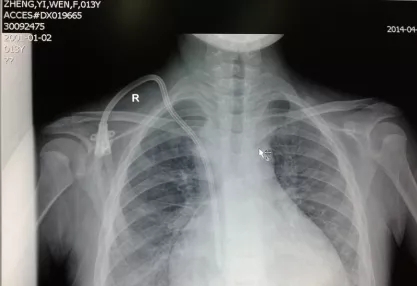

颈外静脉长期导管术后胸部X片▲